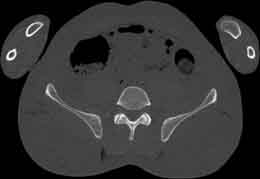

Visible Human male: Sectio transversalis 1756

CT